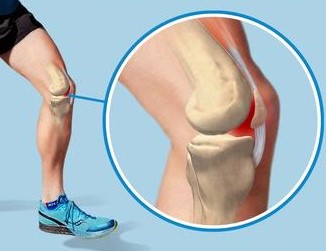

Runner’s knee is more due to abnormal mechanics than a structural issue with the ligaments and cartilage. The kneecap sits in a groove on the femur (thigh bone) lined with thick cartilage. This groove allows for a wide range of motion of the kneecap, but when an impact hits the knee in a flexed position, eg.while running, this forces the kneecap to bump against the groove, increasing stress on the cartilage and causing pain. Running downstairs/downhill and doing squats will increase the impact.

• CHONDROMALACIA PATELLA - the cartilage below the kneecap breaks down due to friction at the back of the knee

• MALALIGNMENT OF BONES from the hips to the ankles - puts excess pressure on certain areas and the kneecap doesn’t move smoothly in the femoral groove

• ANATOMICAL ABNORMALITIES – variations in the shape of the femoral groove and/or kneecap may restrict movement and increase friction due to the two not lining up properly